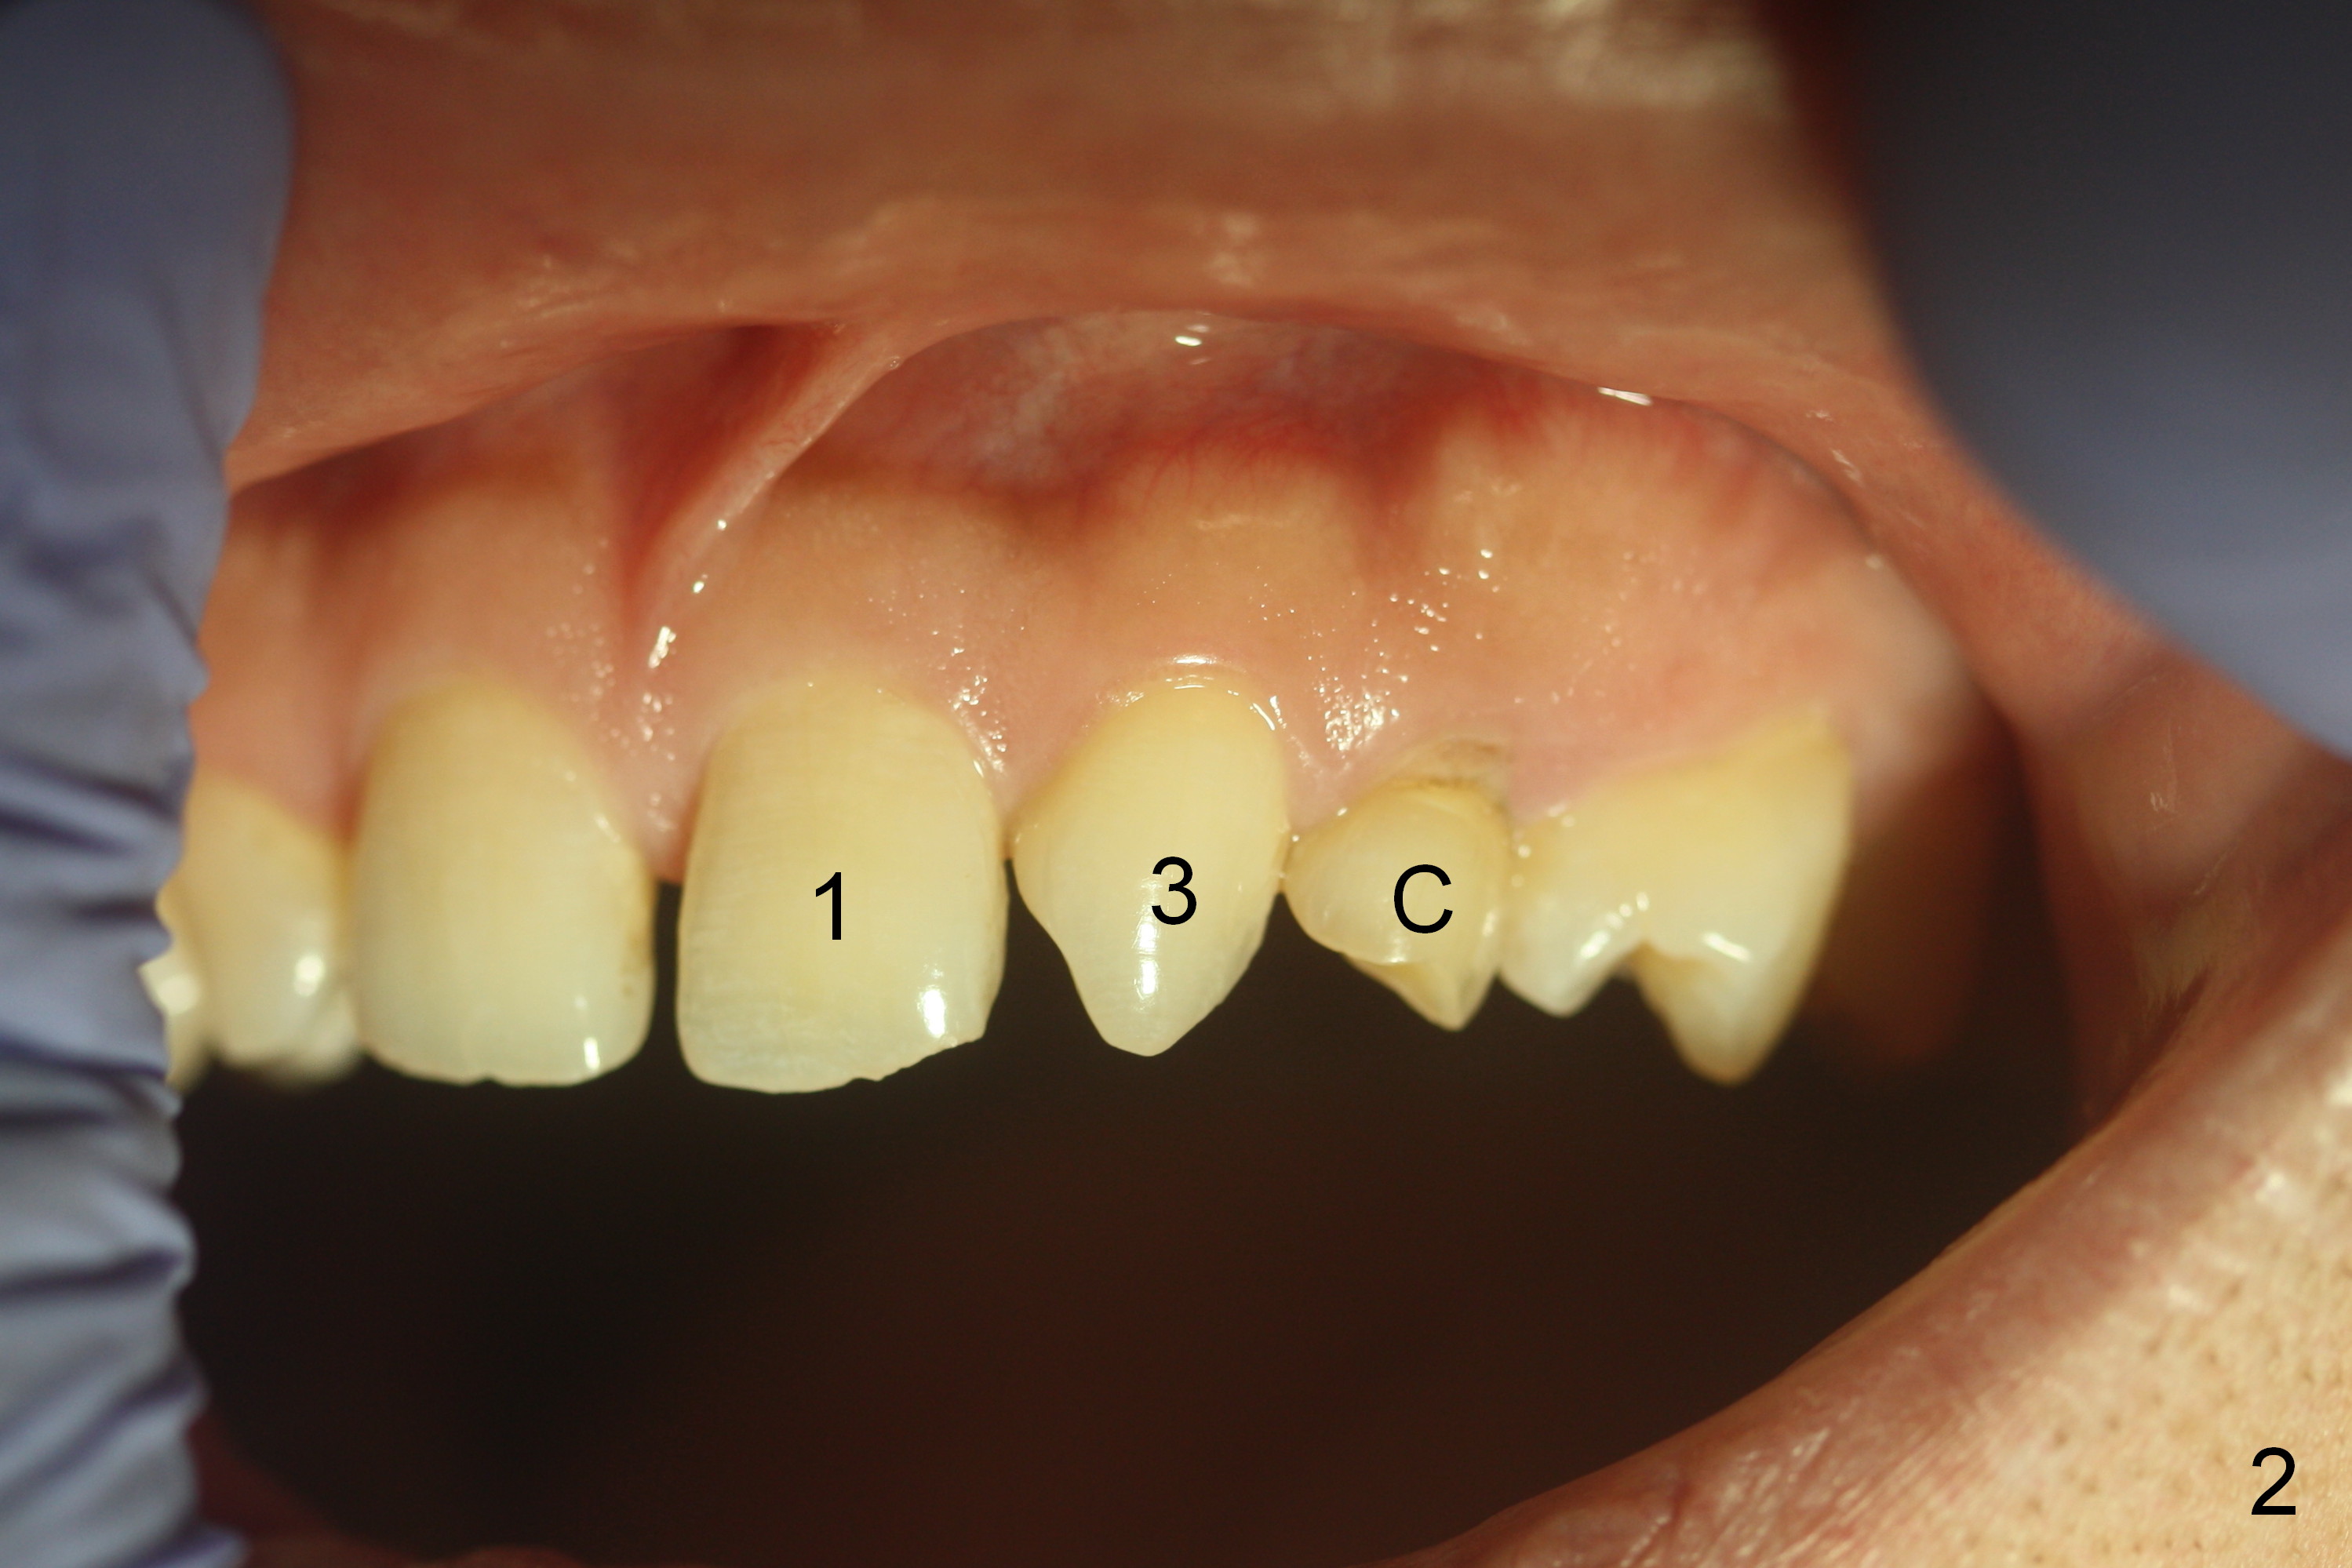

A 38-year-old man has congenitally missing laterals (Fig.1,2) with retention of a deciduous canine (Fig.2,3 C). UL 4 (upper left 1st bicuspid) rotates (Fig.3). LR7 has been extracted (Fig.4).